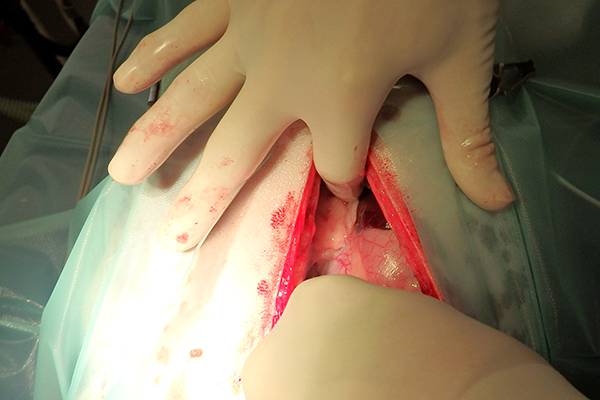

De operatie

Na het openen van de buik en het verwijderen van wat vet, is de chirurg gaan zoeken. Al snel vindt hij aan de voorzijde van de maag een vreemd vliesje. Dit blijkt een stukje vet en vlies te zijn, wat op het oogje van de naald verkleefd zat. Ruim 2/3 van de naald blijkt in een leverlob te zitten. De naald blijkt er niet eenvoudig uitgetrokken te kunnen worden. Hij zit aardig vast. Dit suggereert dat hij er misschien al iets langer zit. Bij het verwijderen van de naald ontstaat er een klein scheurtje in de lever. De bloeding kan worden gestelpt met een speciaal matje dat stolling bevordert. Hierna is het een kwestie van de buik sluiten en Lady mag weer wakker worden.